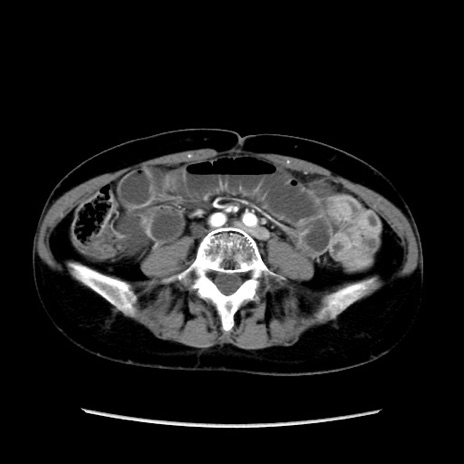

矢状断像

【症例】40歳代 女性

【主訴】上腹部痛、嘔気・嘔吐

【現病歴】約9時間前頃から急に上腹部痛、嘔気、嘔吐が出現。改善しないため救急要請。

【既往歴】子宮頚癌(広汎子宮全摘術、放射線療法)、腸閉塞

【身体所見】腹部:平坦、軟、腸雑音亢進、上腹部を中心に腹部全体に圧痛あり。

【データ】WBC 8400、CRP 0.03